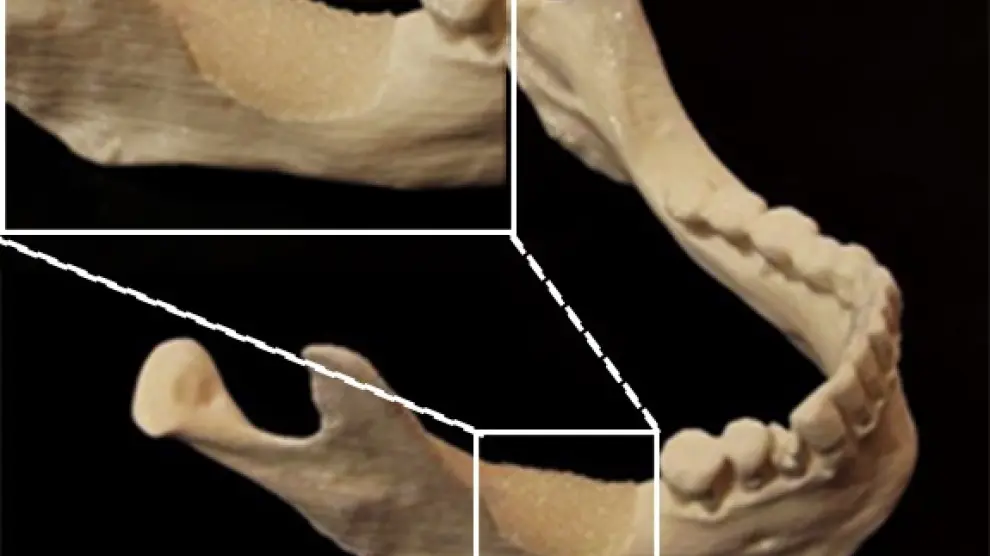

Dichos implantes han sido evaluados in vitro e in vivo en el Instituto Nacional Francés para la Investigación Médica en Estrasburgo, en el grupo de Nadia Jessel, demostrándose en modelos animales que dichos implantes favorecen la regeneración dental y que los dientes regenerados están vascularizados e inervados, dos características necesarias para obtener una buena regeneración.